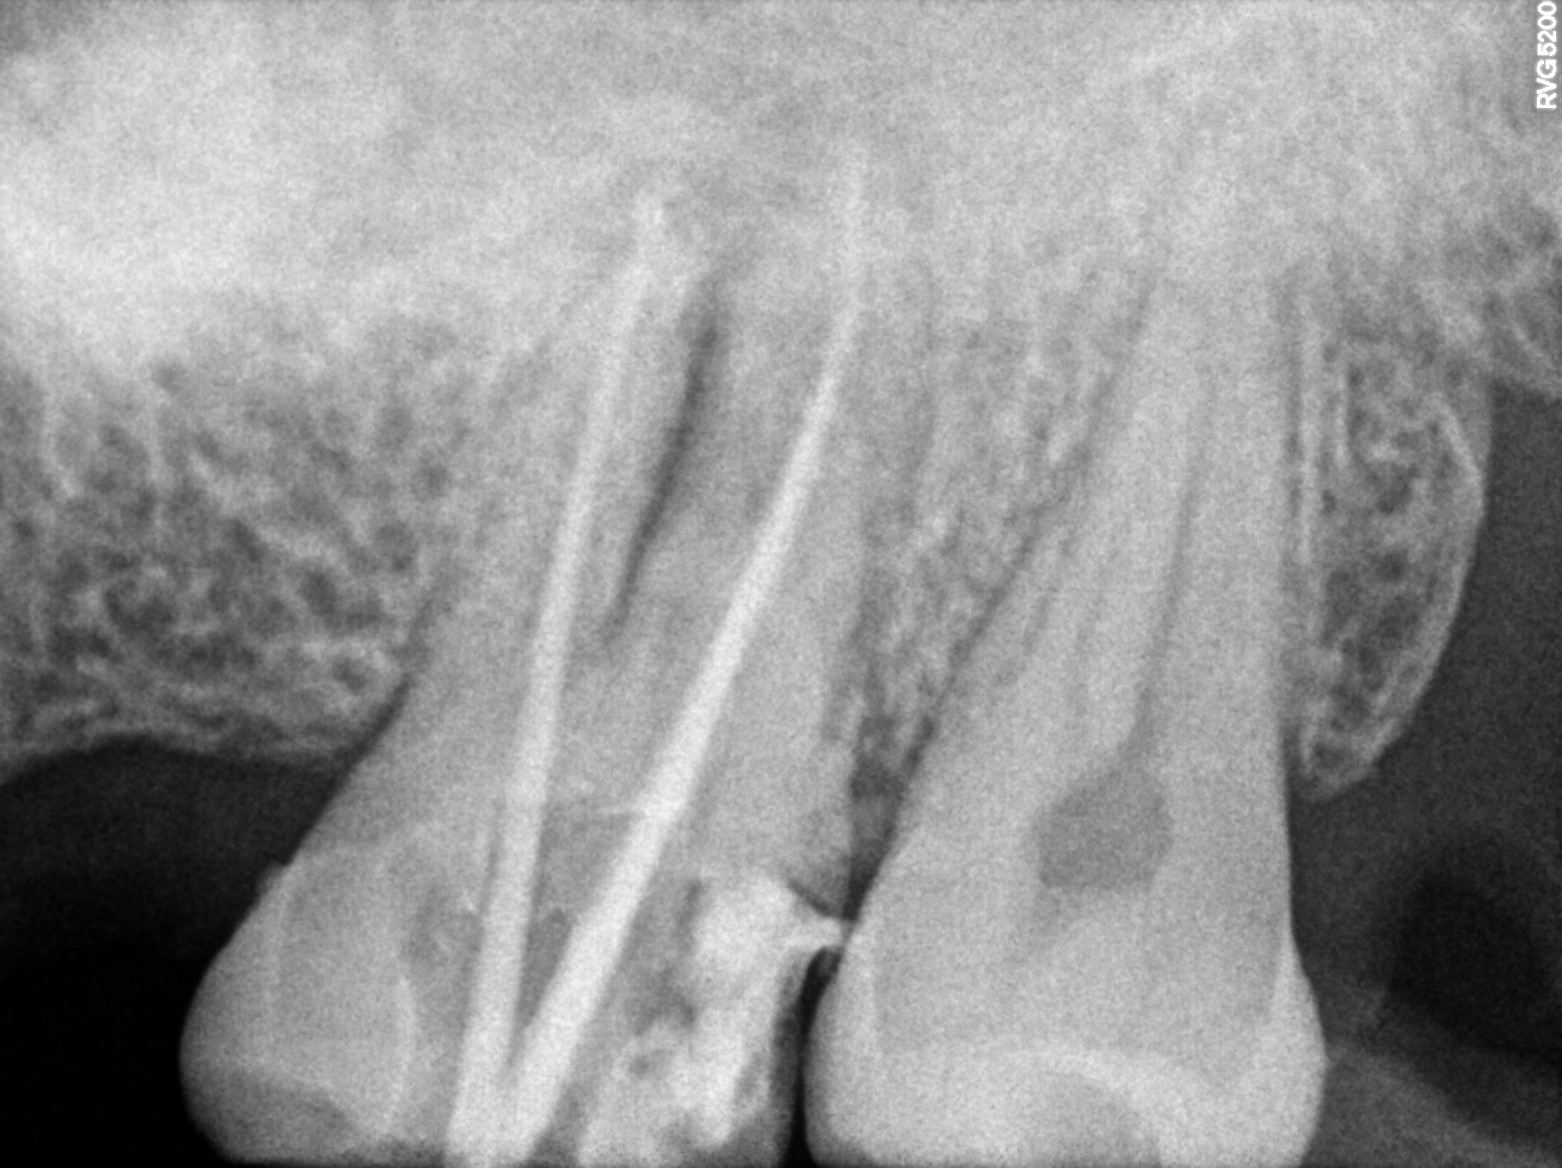

Dental Radiographs FHIR: DocumentReference · LOINC 24641-7

xray_1773075490_1.jpg

24641-7